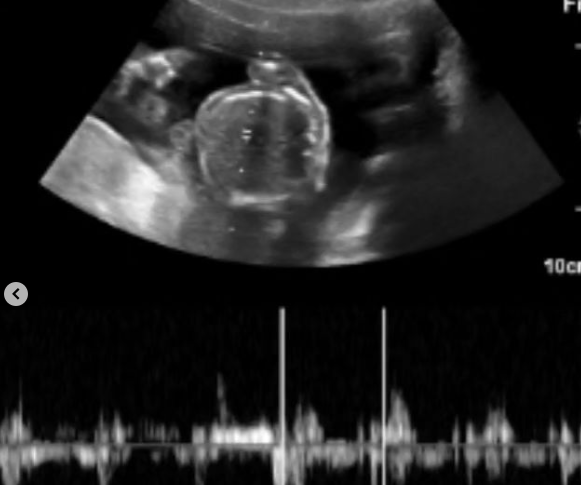

Mamá, a 8 años de tu partida los cielos se abrieron, espero la llegada de mi hija, tu nieta!